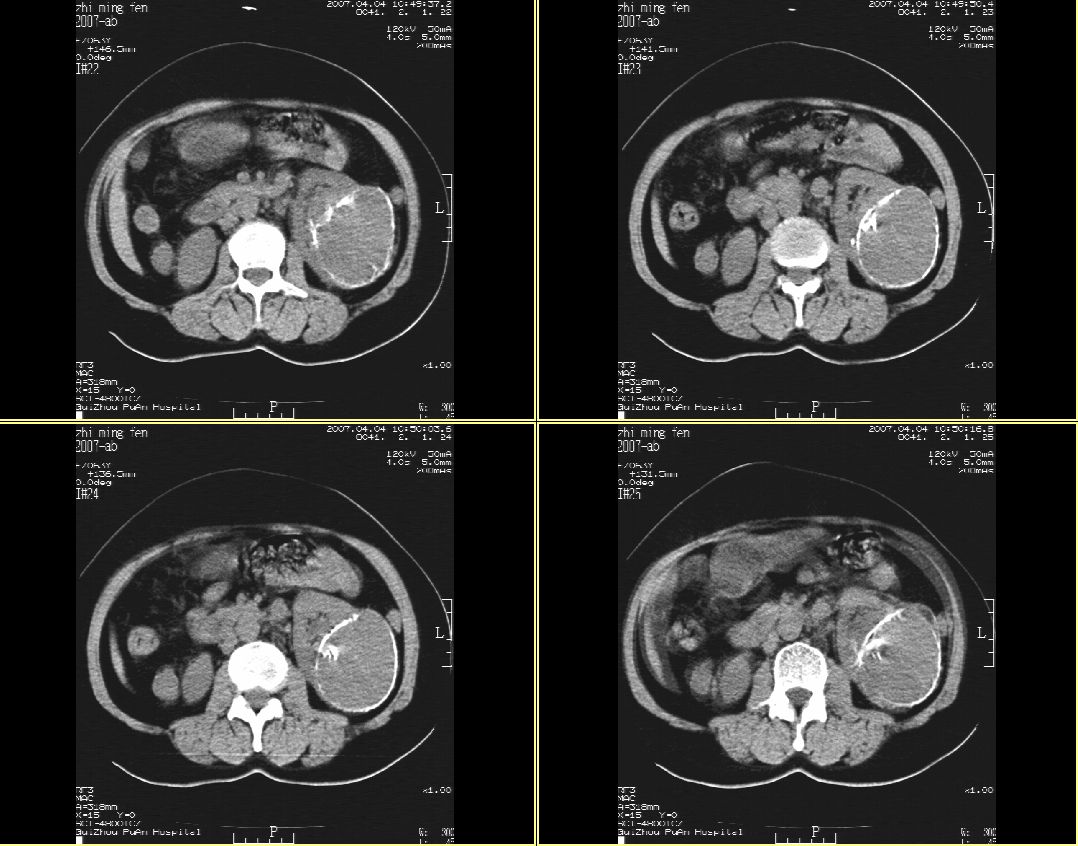

以下是引用hhcckk在2007-4-9 9:18:00的发言:[br]我认为就是一个病灶,病灶上端密度较均匀,下方有明显的钙化,部分呈不完全的环状,考虑肾癌[br]1、肾癌的特征性ct表现为肾实质的占位,局部隆起外突[br]2、肿瘤内的钙化常见,多发生在肿瘤内部,也可以在肿瘤周边呈弧型或不完全的环行钙化[br]3、最常见的三大症状,血尿,腰痛,包块此病人也较符合,增强吧

以下是引用swyyy2007在2007-4-9 18:42:00的发言:[br]支持左肾癌累及肾窦肾盂,左肾积水 [br] [br]